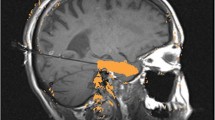

72-year-old with metastatic melanoma. a Sagittal post-contrast T1-weighted imaging before LITT demonstrates a progressing enhancing lesion in the left inferior parietal lobule at a site of a brain metastasis previously treated with gamma knife radiation therapy (long arrow). The lesion was biopsied intraoperatively immediately before LITT and was found to represent radiation necrosis. b Sagittal intraoperative localizing T1-weighted imaging with the laser probe within the lesion (arrowhead). c Sagittal intraoperative gradient-echo phase imaging is the source of the thermography maps. By subtracting subsequent images during heating from a reference image acquired before heating, a map of temperature change can be formed. d Sagittal post-contrast T1-weighted imaging 1 month after LITT demonstrates complete ablation of the lesion (dashed arrow)